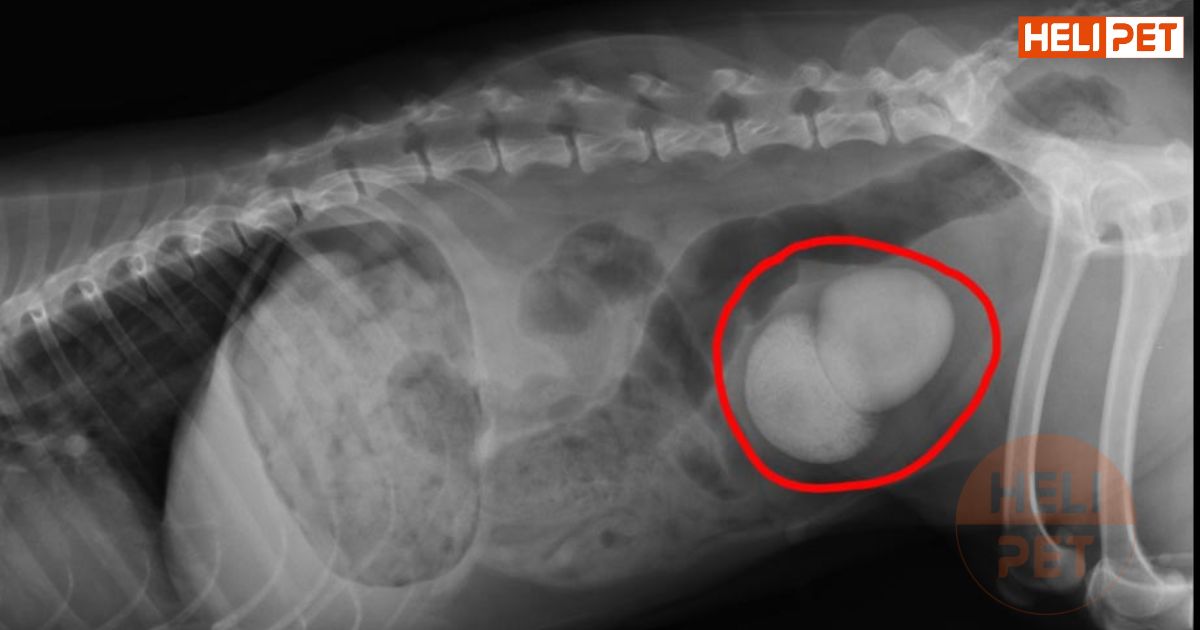

Hình ảnh chụp sỏi bàng quang ở mèo